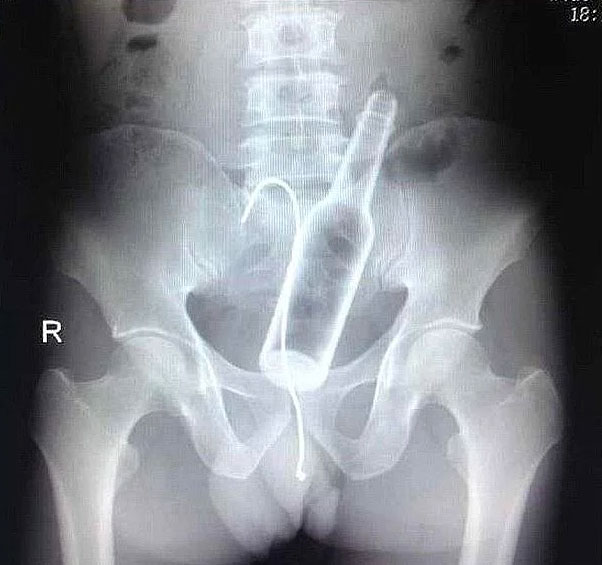

1-) Evet nasıl oldu bilmiyoruz ama hastanın içine cam şişe girmiş…